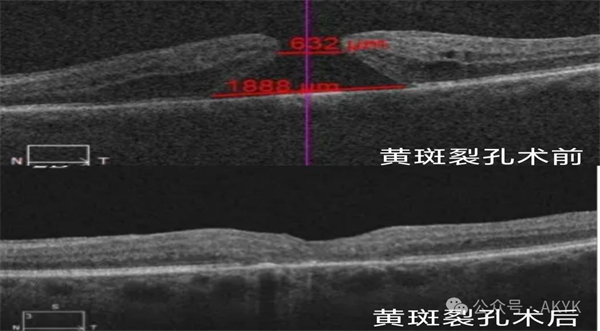

新業(yè)務(wù)二XBs安康新聞網(wǎng)

復(fù)雜黃斑裂孔修復(fù)術(shù):修補(bǔ)裂孔提升視力,降低致盲率。XBs安康新聞網(wǎng)